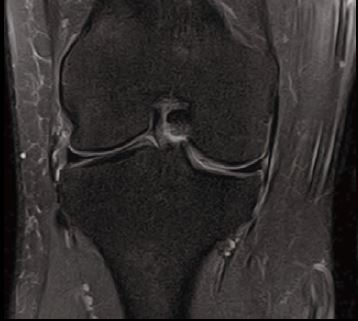

Випадок 3. Сканування коліна лише за 5 хвилин

Чоловік 52 років скаржиться на біль і функціональні порушення за відсутності попередньої травми.

• Внутрішня феморо-тибіальна хондропатія з невеликим внутрішньо суглобовим лопатковим випотом без будь-якої іншої суттєвої аномалії.

Рис. 9 Co FSE PD FS, товщина зрізу 3,5 мм, роздільна здатність 0,6 мм.